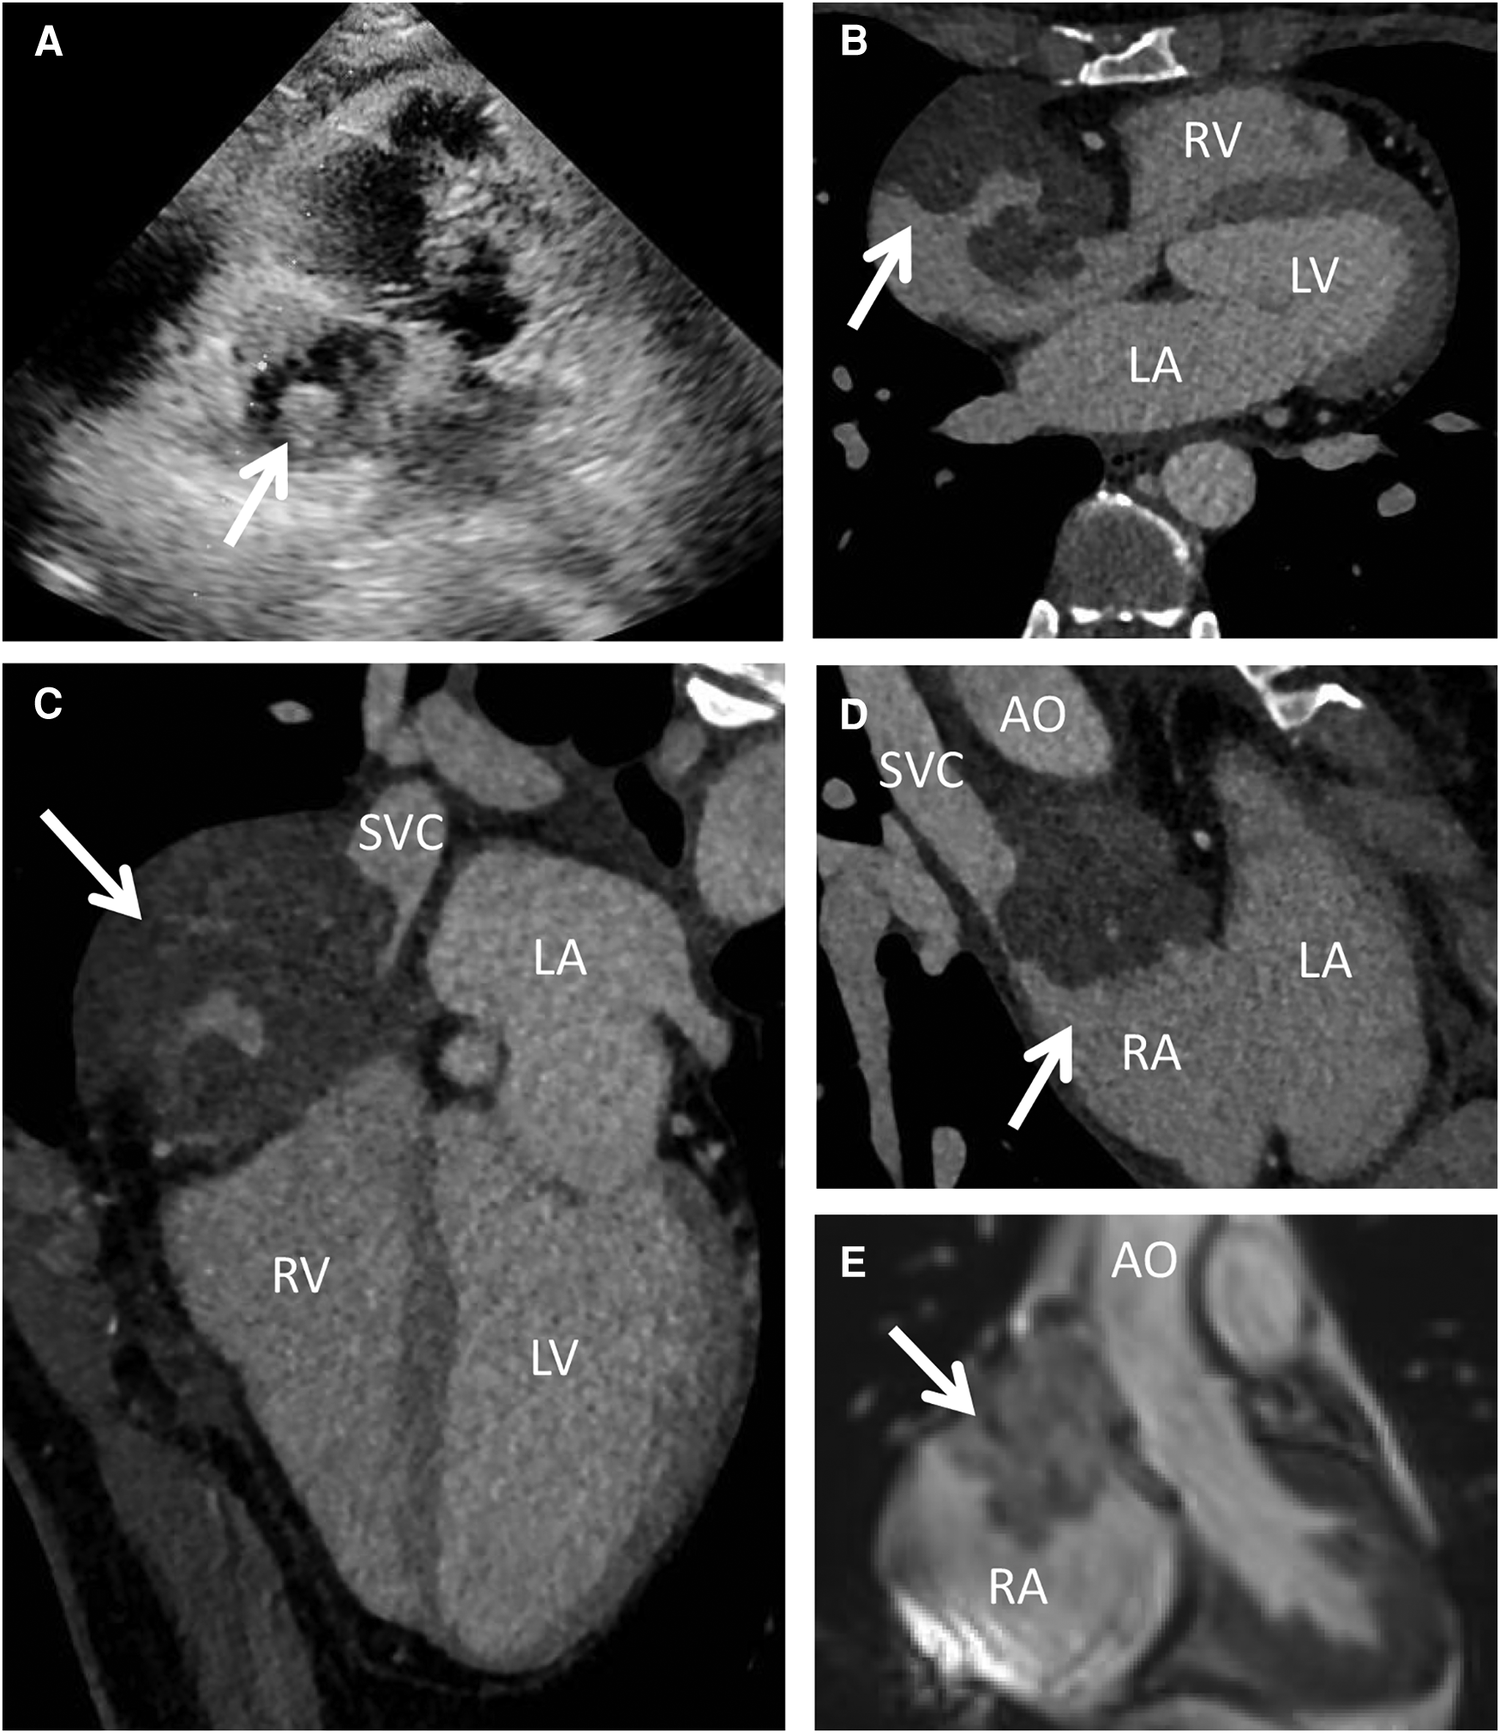

A 44-year-old woman presented with sudden chest discomfort of unknown origin, prompting a comprehensive medical examination conducted one month prior. This examination revealed the presence of a mass in her right atrium. The patient's chest discomfort occurred without accompanying symptoms such as shortness of breath, coughing, or other pulmonary issues. These symptoms typically subsided after a brief 2-minute rest. Through thorough patient interviews, we established the absence of significant medical history and a lack of familial occurrence of similar medical conditions. Notably, prior to admission, a thorough evaluation had unveiled a substantial pericardial effusion, promptly addressed via pericardiocentesis upon admission. No significant abnormal findings were observed in the cytology of the pericardial fluid. Subsequently, a battery of diagnostic procedures was conducted post-admission, encompassing a chest x-ray, cardiac ultrasound, electrocardiogram, cardiac CT, cardiac MRA, and PET-CT. The patient exhibited a normal electrocardiogram indicative of sinus rhythm. Preoperative echocardiography indicated an enlarged heart shadow, delineating multiple masses of uncertain nature in the right atrium, including a minor pericardial effusion (Figure 1A). The cardiac CT highlighted a right atrium lesion with superior vena cava invasion (Figures 1B–D). The cardiac MRA was performed and depicted an occupying lesion in the right atrium, signifying a high likelihood of a malignant tumor (Figure 1E). This assessment was further confirmed by PET-CT findings of multiple nodules with significantly elevated glucose metabolism in the right atrium and concurrent pericardial effusion.

Figure 1

Preoperative echocardiography, cardiac CT and MRI. Echocardiography (A) showed multiple mixed echogenic masses on the lateral wall of the right atrium; CT scan (B–D) showed a giant cardiac mass with the invasion of the RA and SVC; MRI (E) indicated that the mass attached to the wall of RA with unclear boundary. AO, ascending aorta; LA, left atrium; LV, left ventricle; RA, right atrium; RV, right ventricle; SVC, superior vena cava.